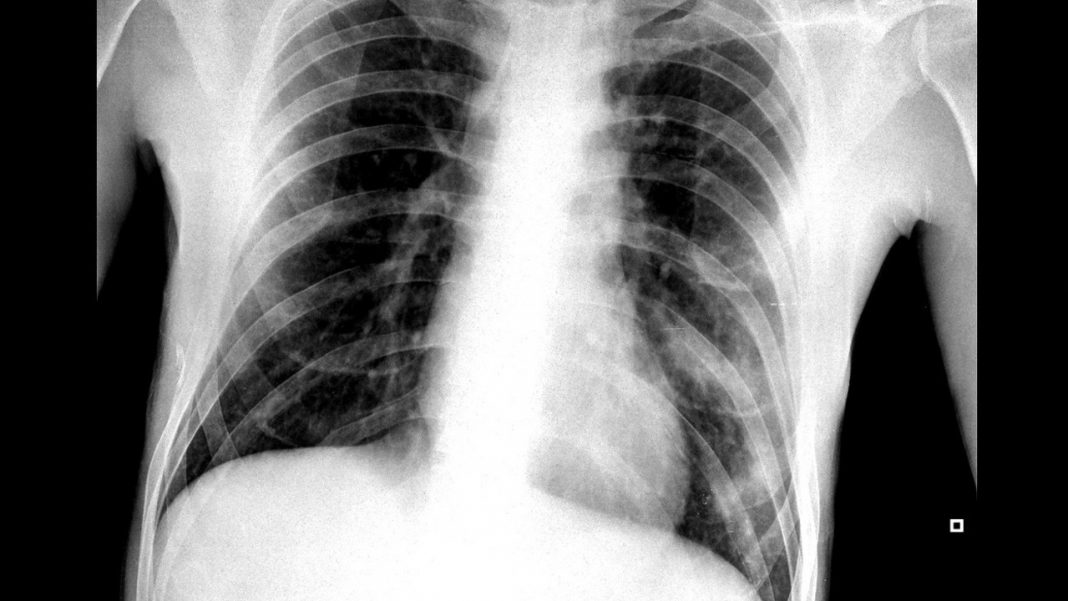

Hoy en día el uso de las radiografías se ha generalizado de tal manera que su uso se extiende a muchas áreas de salud. No obstante, las radiografías están hoy en día en el entredicho.

Y es que, las radiografías, que han supuesto un gran avance para nuestra sociedad gracias a su aplicación médica, suponen un riesgo hoy en día. Pero, ¿por qué? En el siguiente artículo te explico en qué consisten las radiografías y por qué son peligrosas.